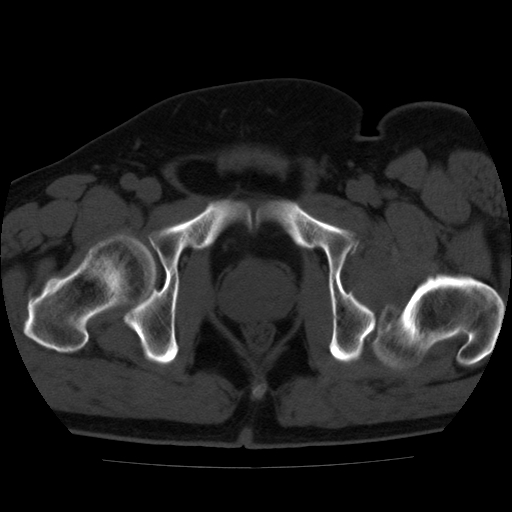

标题: CT21643:男,42岁,车祸伤后左髋关节疼痛剧烈1小时。 [打印本页]

男,42岁,车祸伤后左髋关节疼痛剧烈1小时。

左髋关节脱位并髋臼骨折,左髋关节积血。

左髋关节后脱位并髋臼骨折,左髋关节积血

左髋关节后脱位,大小转子皮质撕脱骨折,关节腔“脂血症”,左侧盆底少量积血,左侧髋臼邻关节囊肿。

左髋关节后脱位并髋臼骨折、股骨头前方骨折,左髋关节积血 。

左髋关节(股骨头)后脱位,并髋臼及股骨头骨折,左髋关节积血。

左髋关节后脱位并髋臼后缘骨折、股骨头前方骨折,左髋关节积血 。我遇到过一例。